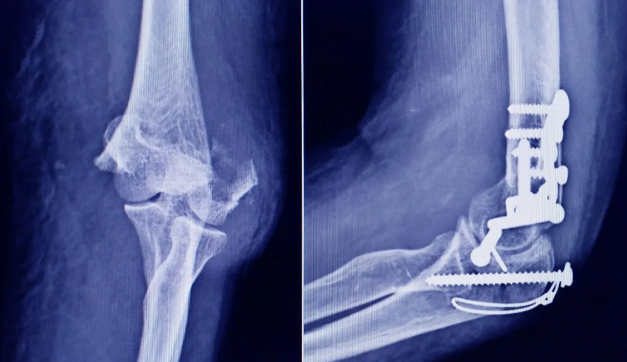

La Administración Nacional de Medicamentos, Alimentos y Tecnología Médica (ANMAT) advirtió a la población por un tornillo utilizado en cirugías traumatológicas debido a que es falso, por lo que su uso representa riesgo para la salud del paciente al que se lo implante.

Se trata de un tornillo utilizado en cirugías traumatológicas que fue detectado durante una inspección de control de mercado realizada en una ortopedia ubicada en la ciudad de San Miguel de Tucumán.

Dicho tornillo es producido por la firma Stryker Corporation, que se encuentra registrada ante ANMAT bajo el PM 594-139. Luego de la inspección, se exhibió la muestra recolectada ante la responsable técnica de dicha empresa, quien afirmó que se trataba de un producto falsificado.

Las autoridades de la ANMAT dieron a conocer las características del producto para su advertencia: STRYKER 10 mm X 28 mm – BIOABSORBABLE – ACL INTERFERENCE SCREW – REF 234-010-067 – LOT 90905.